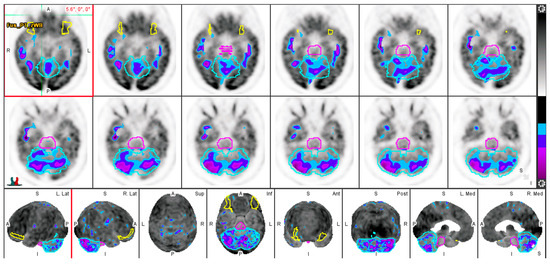

3.3. Effect of Aging on Regional Cerebral Metabolic Activity